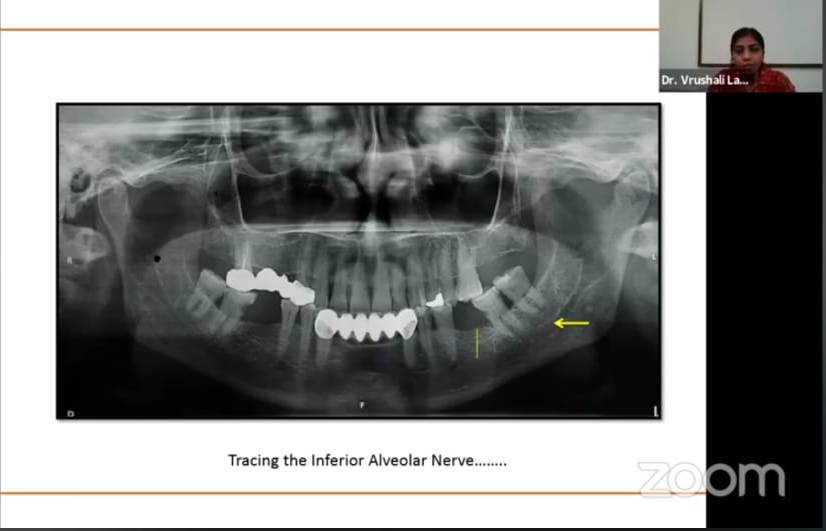

The Guest Speakers for the program on 26th February, 2021 were Dr Rajesh Gaikwad, DrVidya Baliga, Dr Vrushali Lathiya and Moderators were Dr Maya Indurkar, Dr Sangeeta Muglikar, Dr Swapna Mahale. Dr Rajesh Gaikwad conducted lecture on “Clinical diagnostic aids in periodontics” which was moderated by Dr Maya Indurkar, DrVidya Baliga conducted lecture on “Role of biomarkers in periodontal diagnostics” which was moderated by Dr Sangeeta Muglikar. Dr Vrushali Lathiya conducted lecture on “Diagnostic imaging in periodontal disease” which was moderated by Dr Swapna Mahale.

Speaker Dr. Vrushali Lathiya conducting lecture on Diagnostic imaging in periodontal disease